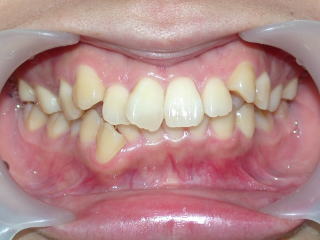

2022年7月25日初診、20代女性の叢生症例 (新潟県長岡市要町 要町歯科 歯科矯正 歯列矯正)

前歯のデコボコが気になる、とのことです。

術前術後

2022年7月→2024年5月(2年弱でした。これから保定期間に入ります。)